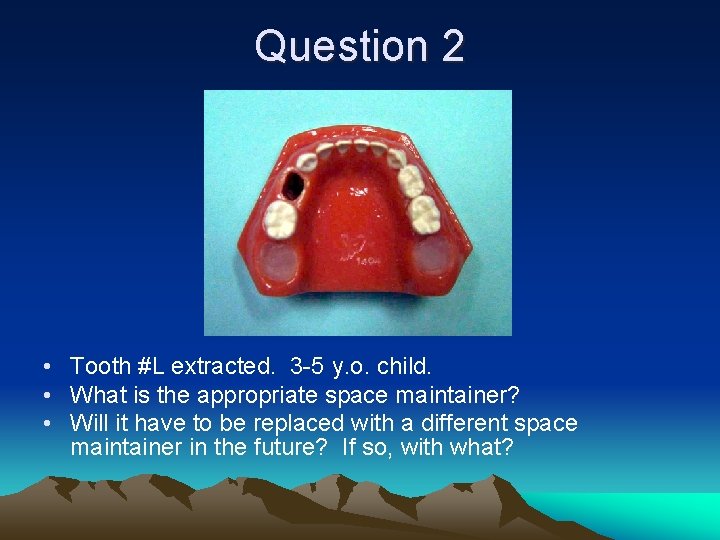

Question 2 • Tooth #L extracted. 3 -5 y. o. child. • What is the appropriate space maintainer? • Will it have to be replaced with a different space maintainer in the future? If so, with what?

Question 2 • Band/Crown Loop #K-M • May need to be replaced by LLHA later. Tooth #M should exfoliate prior to eruption #21.